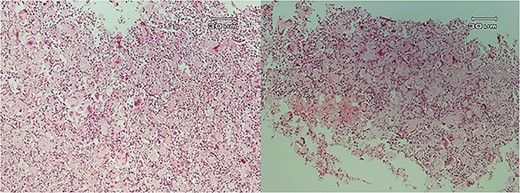

Microscopic examination showed (Figs 4–7) inflamed connective tissue composed of prominent plasma cells mixed with numerous osteoclastic multinucleated giant cells of various sizes with intracytoplasmic asteroid bodies and round Schaumann bodies, which surrounding round to amorphous eosinophilic areas composed of the spindle to stellate cells in fibromyxoid background is also evident.

Histopathologic views of the lesion (H&E staining, ×10 magnification). Inflammation in the connective tissue and foreign body giant cells admixed with severe chronic inflammatory cells.

Histopathologic views of the lesion (H&E staining×100 magnification) showing chronic inflammatory cells admixed with multinucleated giant cells of varying sizes.